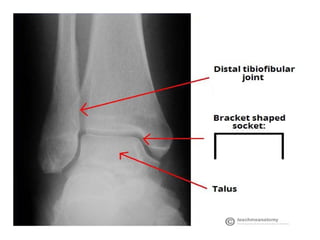

• Articulating Surfaces

• The ankle joint is formed by three bones; the

tibia and fibula of the leg, and the talus of the

foot:

• The tibia and fibula are bound together by

strong tibiofibular ligaments.

• Together, they form a bracket shaped socket,

covered in hyaline cartilage.

• This socket is known as a mortise.

• The body of the talus fits snugly into the

mortise formed by the bones of the leg.

• Articulating Surfaces •The ankle joint is formed by three bones; the tibia and fibula of the leg, and the talus of the foot: • The tibia and fibula are bound together by strong tibiofibular ligaments. • Together, they form a bracket shaped socket, covered in hyaline cartilage. • This socket is known as a mortise.